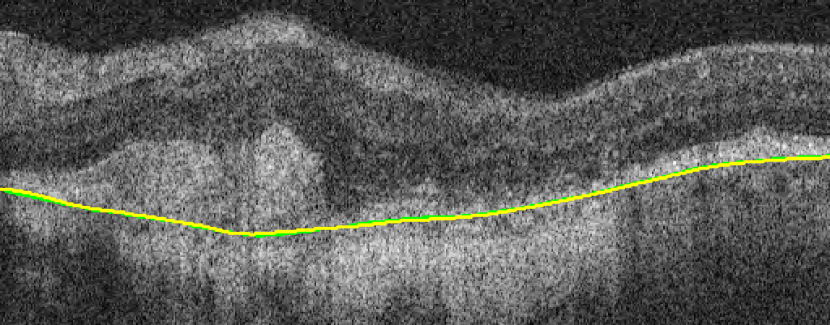

Bruch’s Membrane is an elastic smooth and thin structure, strategically located between the retina and the general circulation, having a crucial role in retinal function, aging and disease [14]. Automated segmentation of the BM is particularly important in the context of AMD as, unlike other common retinal diseases such as DR, RVO, or glaucoma, the BM is distinguishable from the outer RPE boundary. In specific, drusen in iAMD and PEDs in nAMD separate the RPE from BM, requiring the segmentation of the region in-between them. In addition, in case of GA, the RPE is completely lost in some locations, exposing only the BM, thus imposing additional difficulties for algorithms and calculations that depend on the RPE position. Achieving correct automated identification of the BM is challenging in many cases, mainly due to the small thickness of this layer, the high reflectivity of the RPE that shadows parts of the BM, and the noise being present in the scans, which is often indistinguishable from the content of drusen and PEDs (Fig. 4). Due to these difficulties, currently many automated solutions either do not provide a segmentation of the BM or its segmentation is often inaccurate in retinal OCT with AMD, leaving this clinically relevant segmentation task unaddressed or under-explored.

(b) nAMD